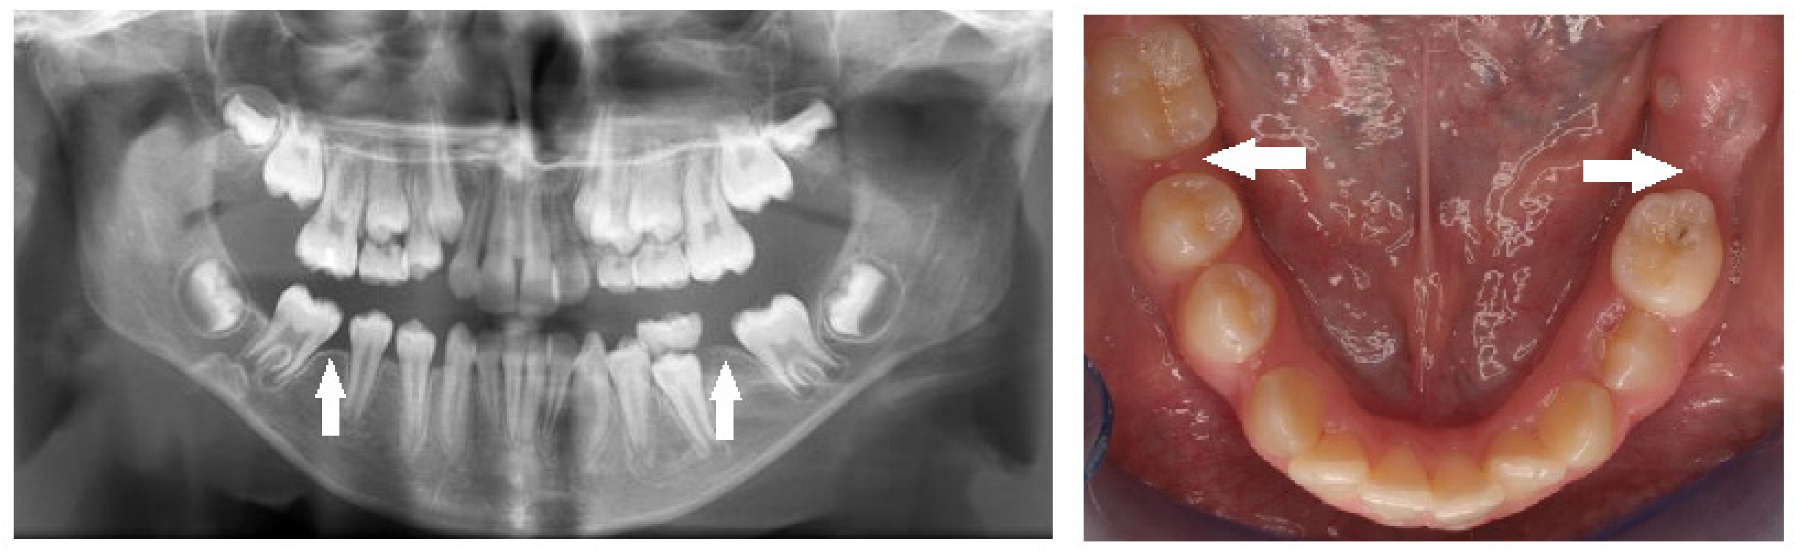

| Submergence | A primary tooth positioned under the occlusal surface of the adjacent teeth. |